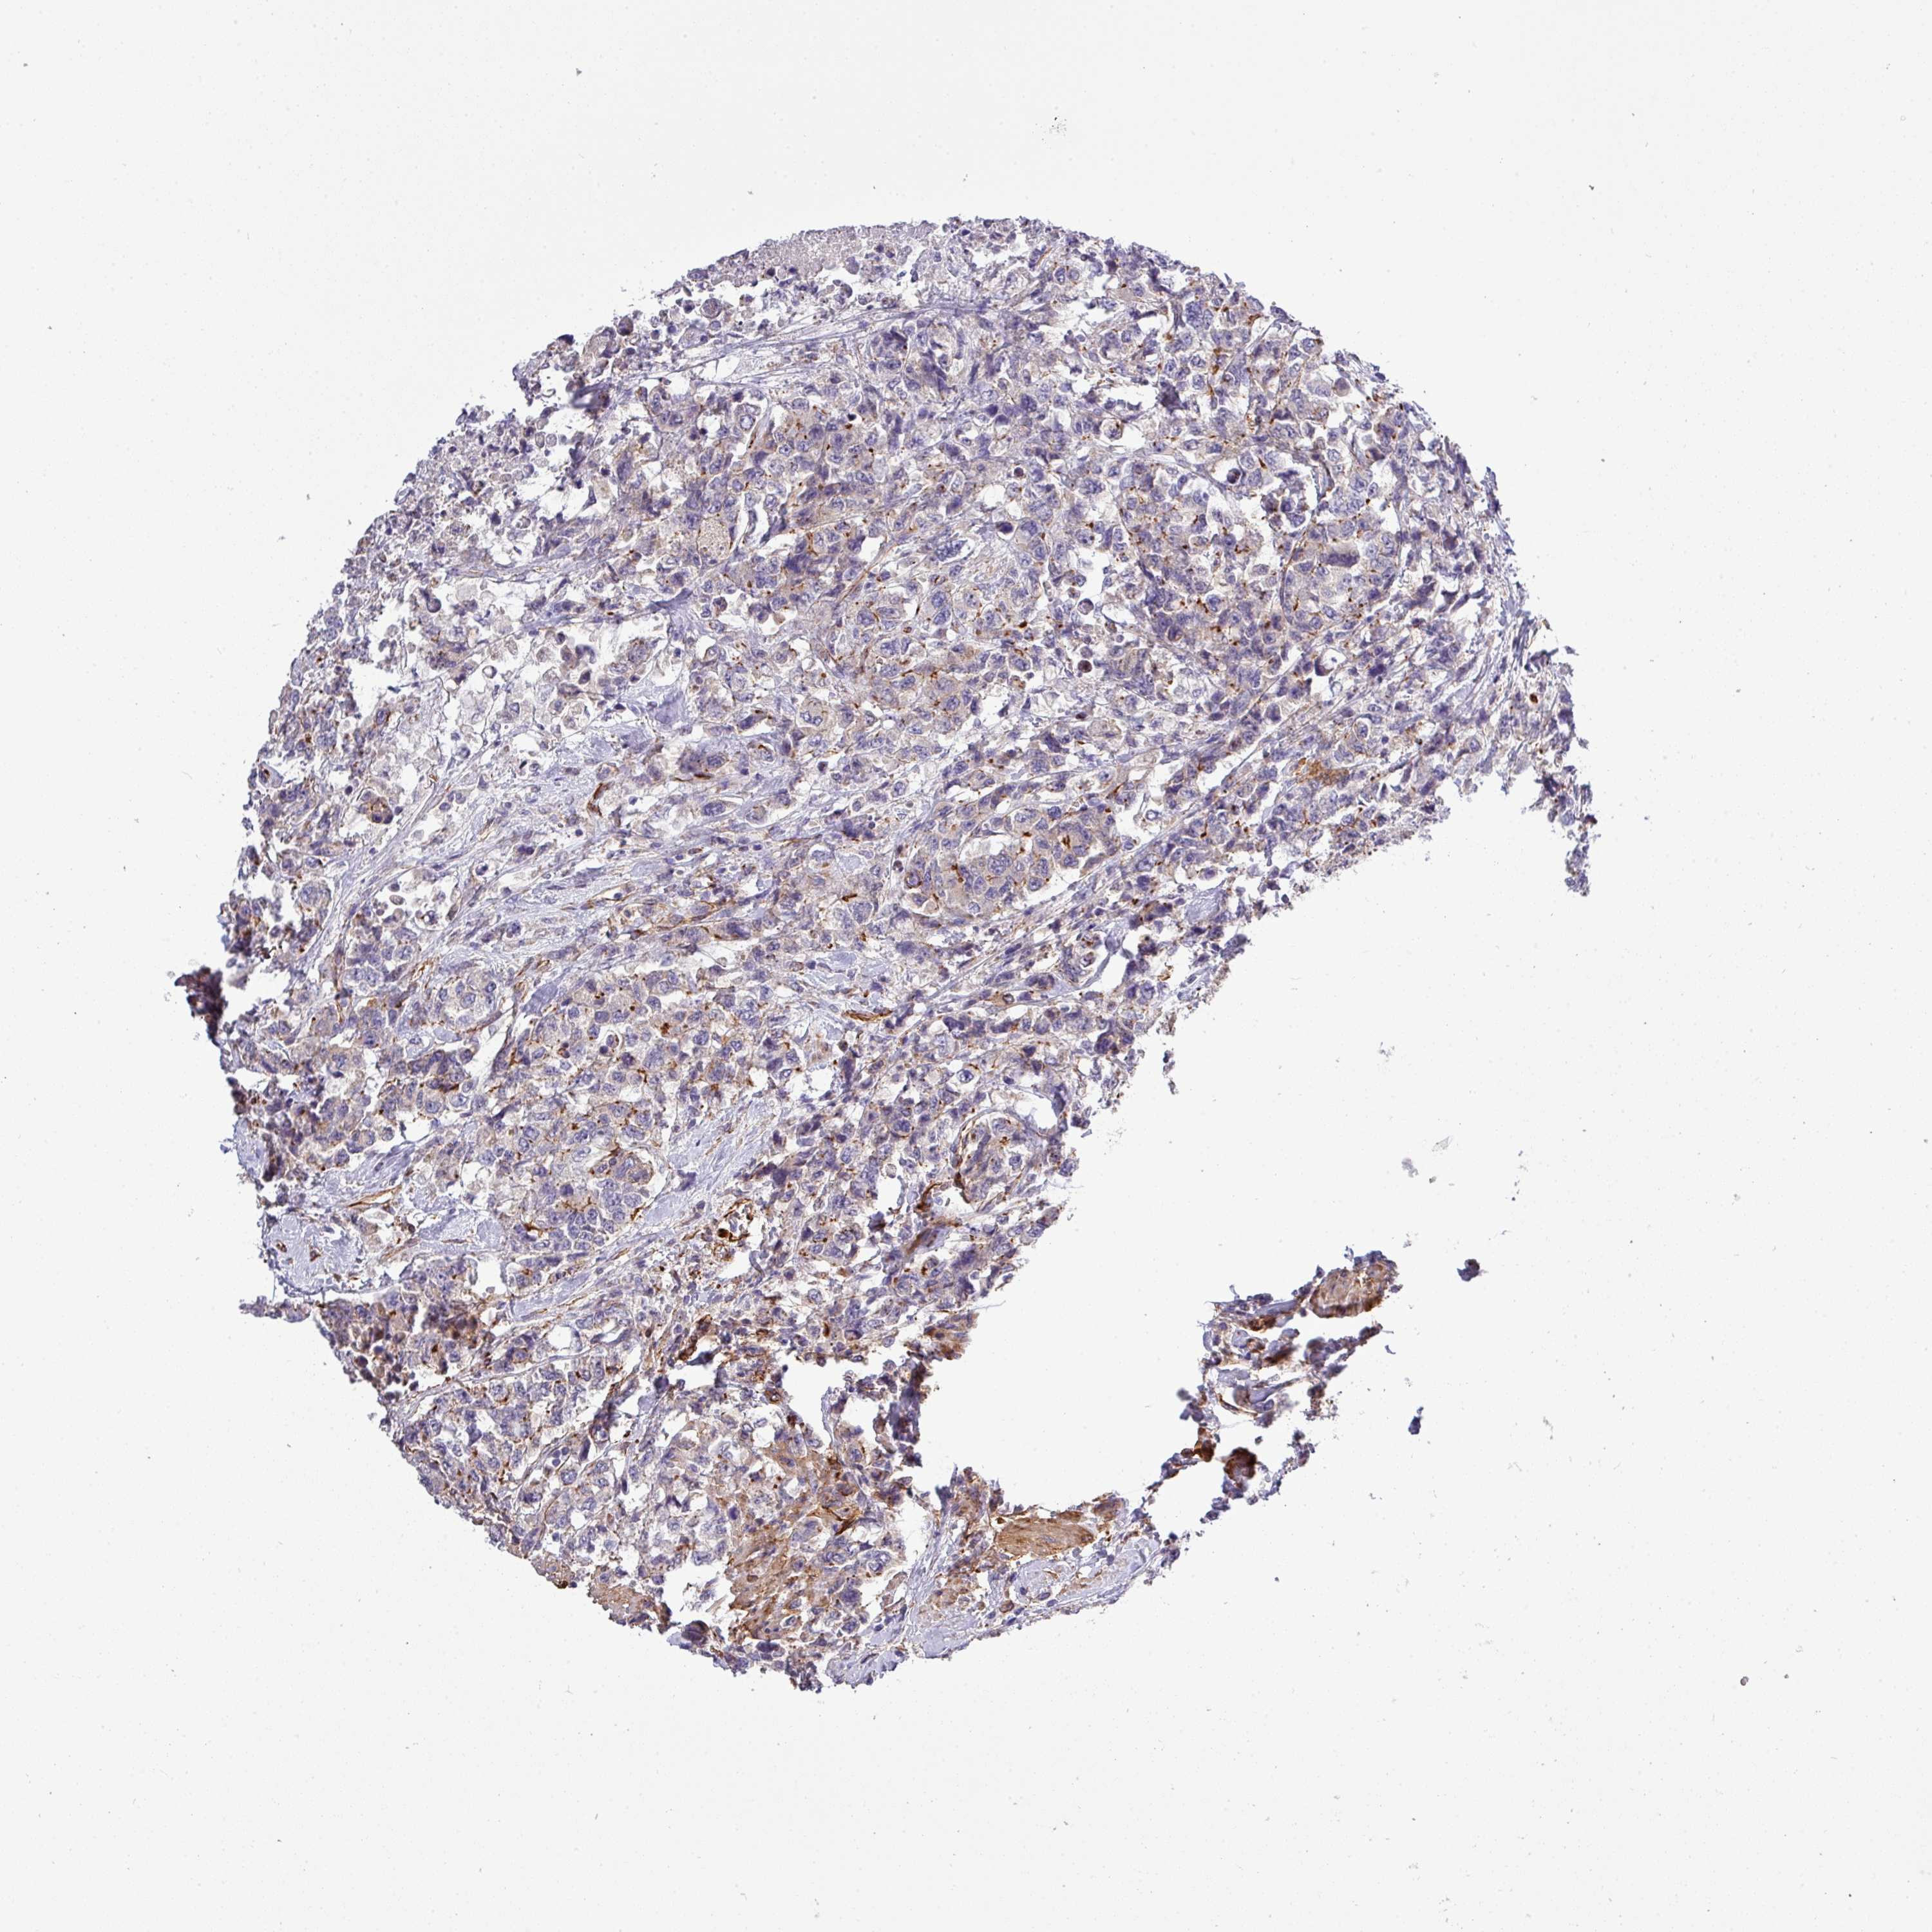

UROTHELIAL CANCER - Protein expressioni

A mouse-over function shows sample information and annotation data. Click on an image to view it in a full screen mode. Samples can be filtered based on level of antibody staining by selecting one or several of the following categories: high, medium, low and not detected. The assay and annotation is described here.

Note that samples used for immunohistochemistry by the Human Protein Atlas do not correspond to samples in the TCGA dataset.

Antibody stainingi

Antibody staining in the annotated cell types in the current human tissue is reported as not detected, low, medium, or high, based on conventional immunohistochemistry profiling in selected tissues. This score is based on the combination of the staining intensity and fraction of stained cells.

Each image is clickable and will lead to virtual microscopy that enables deeper exploration of all samples and also displays staining intensity scores, fraction scores and subcellular localization as well as patient and tissue information for each sample.

Antibody HPA041551

Antibody CAB009733

Urothelial carcinoma, Low grade

Urothelial carcinoma, High grade